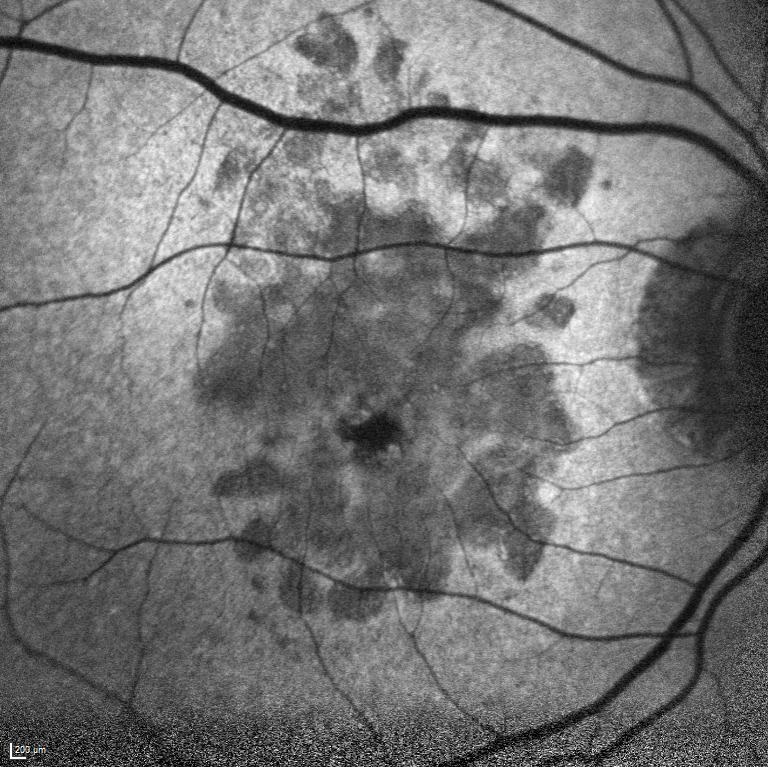

Adölesan Stargardt Hastalığınd ...

Adölesan Stargardt Hastalığında İlk Başarılı Faz 3 Çalışma: Tinlarebant ile Reti ...